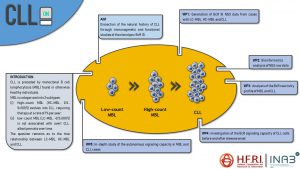

Ακουμιανάκη Αντωνία, Επιστημονική Υπεύθυνη του ερευνητικού έργου με τίτλο: «Διερεύνηση των μηχανισμών δυσλειτουργίας του φαγοσώματος στην ανοσοκαταστολή μετά από σήψη: Ο Δρόμος για Εξατομικευμένη Ιατρική στο Σηπτικό Ασθενή»

Το κλινικό σύνδρομο της σήψης εξακολουθεί να αποτελεί μια από τις κύριες αιτίες θνησιμότητας, νοσηρότητας και αυξημένου κόστους νοσηλείας παγκοσμίως, παρά τη σημαντική πρόοδο που έχει επιτευχθεί στην υποστήριξη των βαρέως πασχόντων ασθενών στις μονάδες εντατικής θεραπείας (ΜΕΘ)…